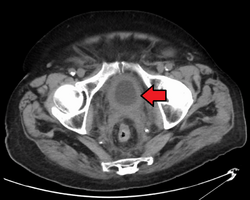

Stage N1 bladder cancer

• N1 Metastasis in a single lymph node in true pelvis (hypogastric, obturator, external iliac, or presacral nodes)

The most common sites for bladder cancer metastases are the lymph nodes, bones, lung, liver, and peritoneum.[78] The most common sentinel lymph nodes draining bladder cancer are obturator and internal iliac lymph nodes. The location of lymphatic spread depends on the location of the tumors. Tumors on the superolateral bladder wall spread to external iliac lymph nodes. Tumors on the neck, anterior wall and fundus spread commonly to the internal iliac lymph nodes.[79] From the regional lymph nodes (i.e. obturator, internal and external lymph nodes) the cancer spreads to distant sites like the common iliac lymph nodes and paraaortic lymph nodes.[80] Skipped lymph node lesions are not seen in bladder cancer.[79]